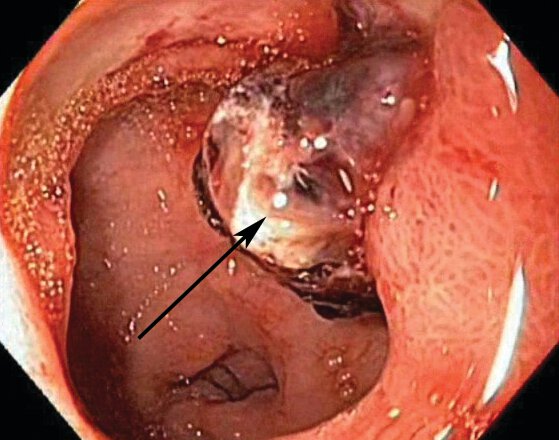

Identify EGD finding pointed by the arrow.

Duodenal ulcer with adherent clot (arrow) that is at risk for rebleeding. This can be treated medically or by clot removal and endoscopic therapy in addition to standard medical therapy.